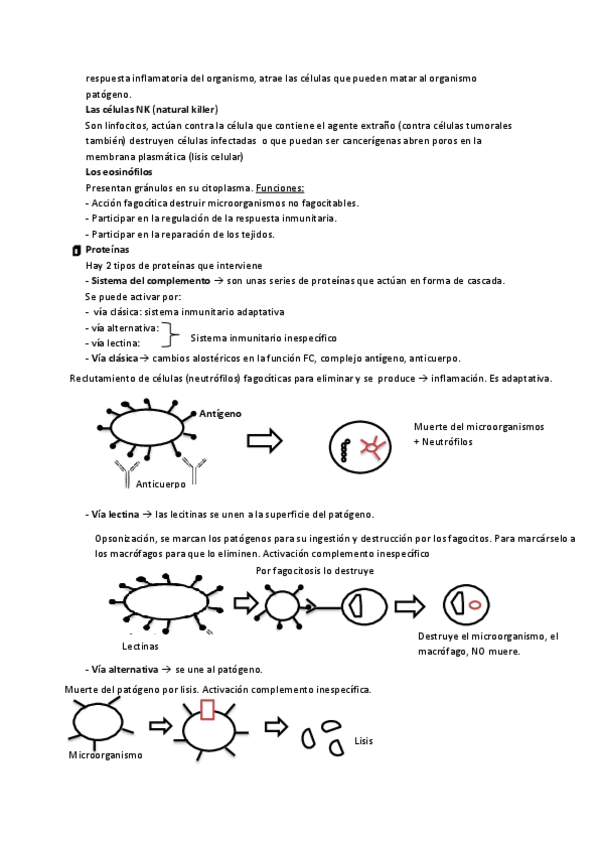

He publicado nuevos apuntes de Fisiopatología general: Tema-6-Los-mecanismos-de-defensa-del-organismo.pdf